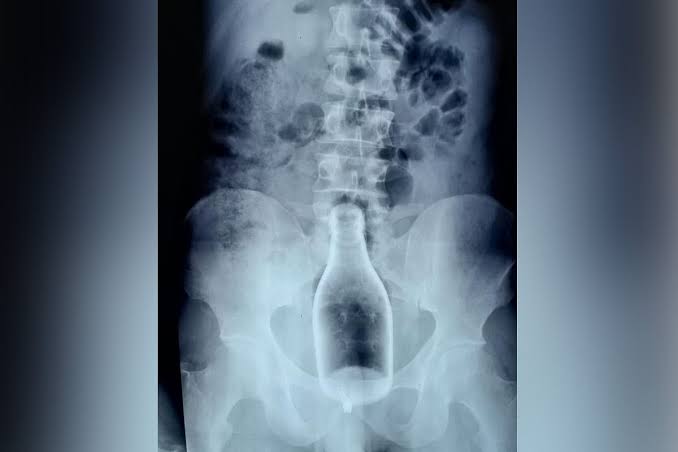

>On 1 May 1985, Đorđe Martinović, a 56-year-old resident of the Kosovar town of Gjilan, arrived at the local hospital with a broken bottle wedged in his rectum. He claimed that he had been attacked by two Albanian men while he was working in his field. After being interrogated by a Yugoslav People's Army colonel, Martinović reportedly admitted that his injuries had been self-inflicted in a botched attempt at masturbation. Public investigators reported that "the prosecutor made a written conclusion from which it appears that the wounded performed an act of 'self-satisfaction' in his field, [that he] put an empty glass bottle of sparkling water[2] on a wooden stick and stuck it in the ground. After that he sat 'on the bottle and enjoyed'."[1] Community leaders in Gjilan subsequently issued a statement describing his injuries as the "accidental consequences of a self-induced [sexual] practice".[3]

>He was transferred to Belgrade for further investigations at the prestigious Military Medical Academy, but a medical team there reported that his injuries were not consistent with a self-inflicted wound. The team, which included two doctors from Belgrade and one each from Ljubljana, Zagreb, and Skopje (thus representing four of Yugoslavia's six republics), concluded that the injuries had been caused "by a strong, brutal and sudden insertion or jamming of a 500 ml. bottle, or rather, its wider end, into the rectum" and that it was probably physically impossible for Martinović to have done this to himself. The team argued that the insertion "could only have been carried out by at least two or more individuals."[3]